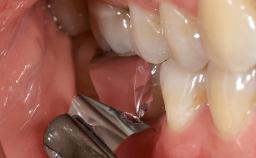

Treatment of Peri-Implantitis at a Zirconia Implant

Due to their promising clinical performance, zirconia implants have recently become popular alternatives to titanium implants, particularly for areas with high esthetic demands (Holländer and coworkers 2016; Roehling and coworkers 2016; Lorenz and coworkers 2019). However, regardless of the reported high survival and success rates, zirconia implants were affected by peri-implant diseases over the short observation period, suggesting the importance of treating peri-implant diseases at zirconia implants (Becker and coworkers 2017). In their case, Frank Schwarz and Ausra Ramanauskaite present 3-year results following mechanical debridement alongside Er:YAG laser monotherapy.